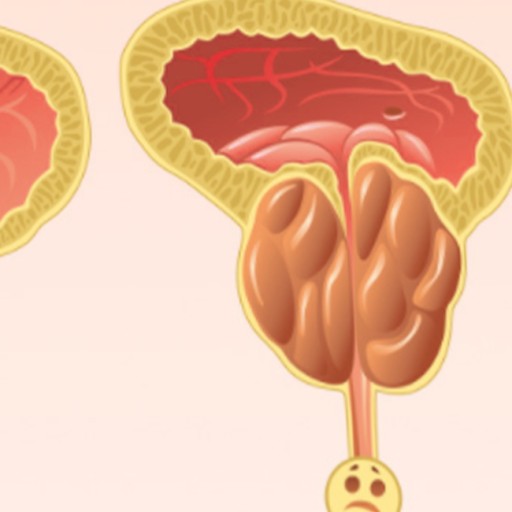

전립선암 초기증상 전립선암 발병 위험이 높은 남자나이나 일정 연령 이상의 남자는 특히나 더 조심해야 하고 항상 신경 써야 해요. 전립선암은 남자의 생식기관에 위치한 작은 샘인 전립선에 발생하는 암의 일종인데요. 전립선은 정자에 영양을 공급하고 지켜주는 체액을 생산하고 분비하는 할 일을 해요. 전립선암은 전립선의 비정상 세포가 성장하고 통제할 수 없이 증식해서 종양을 형성할 때 발생해요.

전립선암은 느리게 성장할 수 있으며 초기 단계에서는 무증상인 그럴 경우가 많아요. 그러나 암이 자라서 전립선을 넘어 전이된다면 배뇨 곤란, 소변 또는 정액의 혈액, 뼈 고통 및 피로와 같은 심각한 고통을 일으킬 수 있어요.